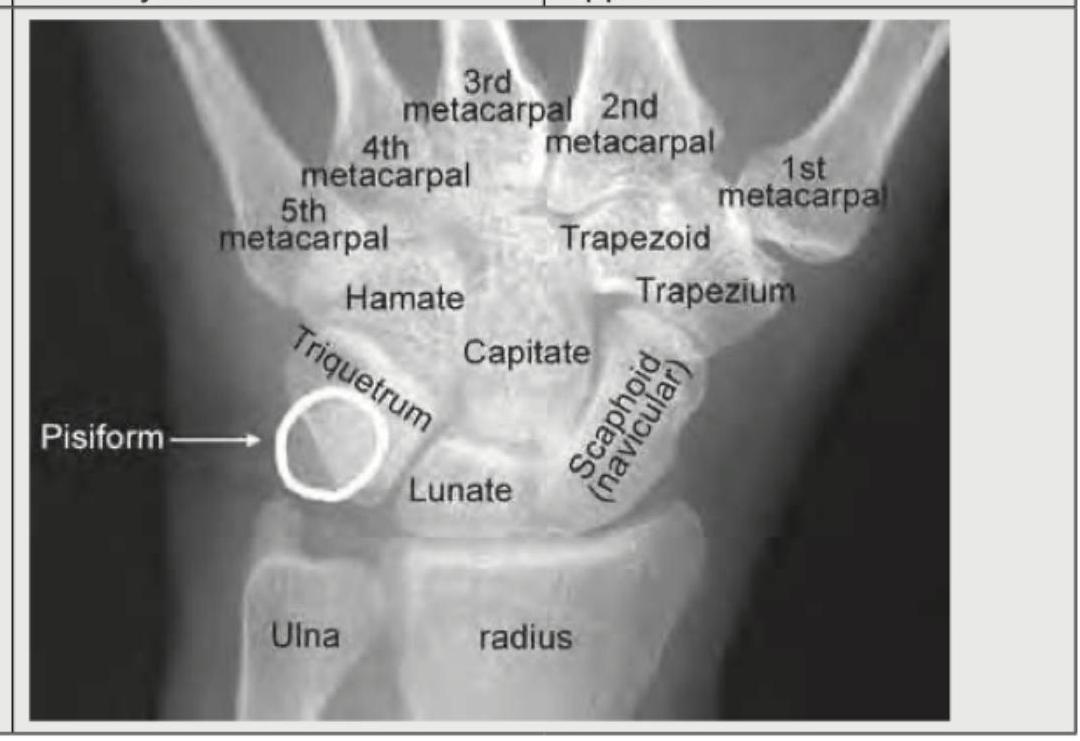

The image shows ossification centers at the lower end of the radius and ulna which are not fused, and the pisiform is present. Based on this, what is the most accurate conclusion about the age?

Explanation: **14-16 years** - The presence of the **pisiform** and unfused epiphyses at the **distal radius and ulna** is consistent with an age range of 14-16 years. The pisiform typically begins to ossify around 10-12 years in females and 12-14 years in males, while the distal radial and ulnar epiphyses usually fuse later, completing closure around 16-18 years. - In females, the distal radius begins ossifying around **12-14 years** and fuses around **16-17 years**. In males, it starts ossifying around 14 years and fuses around 17-18 years. The ulna follows a similar pattern, typically fusing a bit later than the radius. *<12 years* - While the pisiform may begin to ossify in some individuals around 10-12 years, the **distal radial and ulnar epiphyses are generally still widely open** and not yet nearing fusion at this age. - Many carpal bones would still be in earlier stages of development, and the overall skeletal maturity would be less advanced than depicted. *12-14 years* - During this period, the **pisiform is usually ossified**, but the **fusion of the distal radius and ulna has not typically begun**. The image shows the epiphyses of the radius and ulna are present but not yet fused, suggesting a slightly older age than 12-14 years, especially considering the advanced development of other carpal bones. - The epiphyses appear well-formed and distinct, indicating a stage where fusion is approaching but not yet initiated, which is usually after 14 years. *<17.5 years* - While this option is technically correct in that 14-16 years is less than 17.5 years, it is too broad and not the **most accurate conclusion**. The specific features like the absence of fusion in the distal radius and ulna help narrow down the age range more precisely. - After 17.5 years, especially in males, the **distal radial and ulnar epiphyses** would typically show signs of complete or near-complete fusion.